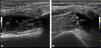

Musculoskeletal ultrasound is a safe and easily accessible imaging technique that allows the study of suspected infections of the musculoskeletal system. Although no finding is specific to these types of processes, certain synovial characteristics may suggest an infectious process rather than a non-infectious inflammatory condition. The role of ultrasound in this group of diseases is also to facilitate the extraction of synovial fluid for microbiological study. Ultrasound-guided synovial tissue biopsy is a minimally invasive, feasible, safe, and well-tolerated procedure that provides high-quality tissue samples, enhancing diagnostic capabilities in cases of suspected infectious arthritis, especially when synovial fluid analysis is negative or inconclusive.